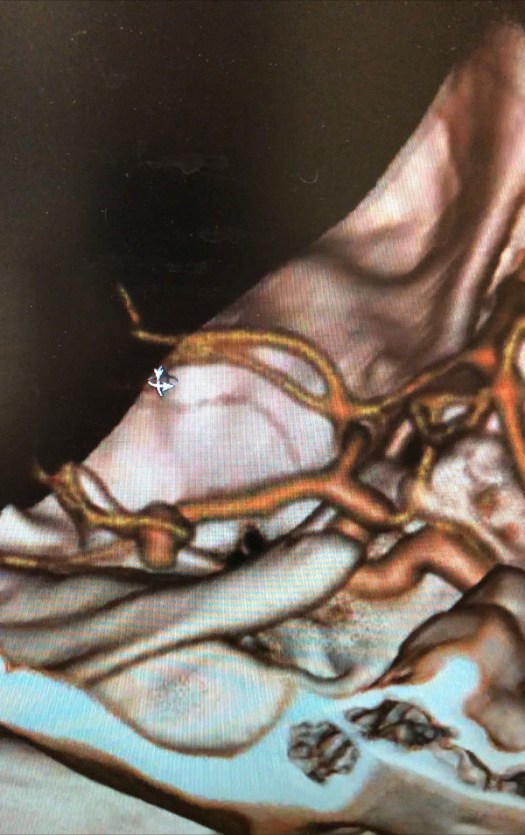

Clipping di aneurisma complesso M1-M2 di sinistra – ricostruzione biforcazione arteria cerebrale media

Angiografia cerebrale di controllo post-operatorio